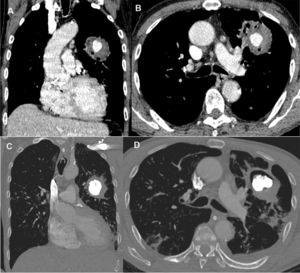

Enhanced coronal (A) and axial (B) computed tomography images showing an inhomogeneous round opacity in the left upper lobe, with a nodular formation showing intense contrast uptake inside, compatible with Rasmussen's aneurysm. Enhanced coronal (C) and axial (D) computed tomography images acquired 48h after treatment demonstrated the adequate filling of the Rasmussen's aneurysm with embolizing material, with no indication of new bleeding.

A 65-year-old man recently diagnosed with pulmonary tuberculosis presented to the emergency department due to cough and daily hemoptysis episodes (50–100ml blood/episode). While hospitalized, he experienced a severe massive bleeding episode, prompting emergency fiberoptic bronchoscopy that revealed a clot obstructing the left main bronchus. Chest computed tomography demonstrated the presence of a round opacity in the left upper lobe, with a nodular formation with intense contrast uptake inside, compatible with Rasmussen aneurysm (RA; Fig. 1A and B). The patient underwent angiography of the pulmonary and bronchial arteries, which did not demonstrate aneurysmal formation. Ultrasound-guided aneurysmal sac puncture using a 22G Chiba needle and percutaneous embolization with a cyanoacrylate/Lipiodol® solution under fluoroscopic visualization were performed. The RA was adequately filled with embolizing material (Fig. 1C and D). The patient was discharged 3 days after the procedure, and was completely asymptomatic after 1 year of follow up. Tuberculosis is a significant cause of hemoptysis globally, especially in developing countries, and RA is a rare but life-threatening complication. For most cases of RA, especially those with life-threatening hemoptysis, safer and less-invasive endovascular therapy with embolization has replaced surgical intervention. In some cases, however, percutaneous injection therapy can be considered because embolization of the pulmonary or bronchial arteries alone may fail to control the hemoptysis.1,2